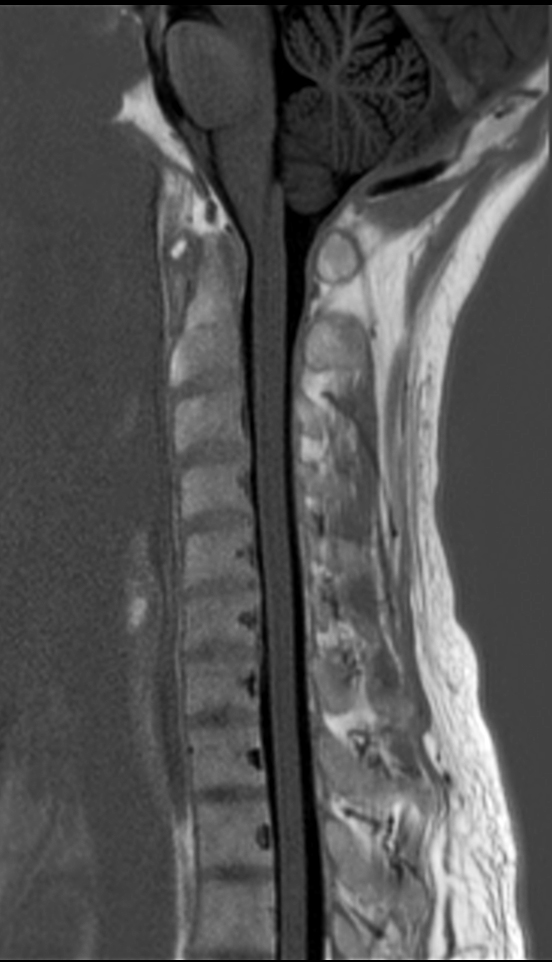

Sagittal T1w mDIXON TSE (In Phase)

Sagittal T2w mDIXON TSE (In Phase)